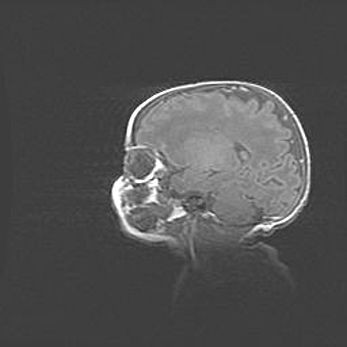

Церебральная ишемия II.

Возраст: 7 дней

Вес: 3350 г

Пол: женский

Окружность головы: 35 см

Срок гестации: 39 недель

Ишемия головного мозга – это состояние, которое развивается в ответ на кислородное голодание вследствие недостаточного мозгового кровообращения. У новорожденных она является следствием дефицита кислорода, что ведет к метаболическим расстройствам различной степени тяжести в тканях головного мозга, в том числе к развитию коагуляционных некрозов и гибели нейронов.